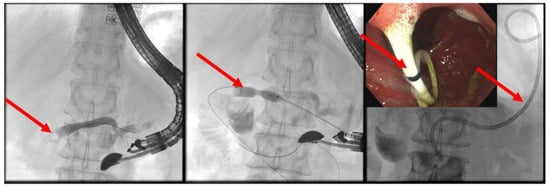

(C) EUS-guided internal antegrade pancreatic duct drainage: In cases where the papilla or anastomosis cannot be accessed, a wire is inserted following the puncture of the pancreatic duct. Subsequently, an HF ring knife (MTW Endoskopie Manufaktur W. Haag KG, Wesel, Germany) is introduced via the wire, which can also be employed to overcome challenging strictures with specialized wires, as there is no risk of wire ablation. If the stricture at the anastomosis can be passed, an 8- to 15-mm dilatation balloon is inserted to dilate the stenosis (refer to Figure 9). Additionally, a long pigtail (14 cm, 8.5 French) can be inserted as jejuno-pancreatico-gastrostomy (ring drainage) to secure the dilatation effect, which can be removed after approximately 8–12 weeks.

Figure 9. Post-pancreatojejunostomy resection—remitting pain—dilated pancreatic duct; transgastric puncture of the pancreatic duct—demonstration of a pancreaticolith (red arrow, to the anastomotic stenosis (left panel); balloon dilation (red arrow) of the stenosis, advancement of the stone in push technique (middle panel); placement of jejuno-pancreatico-gastrostomy drainage (red arrows; 8.5-Fr. double pigtail); right panel (satellite panel, endoscopic control view), selected from the clinical picture library of the reporting Dept. of Gastroenterology, Hepatology and General Internal Medicine.